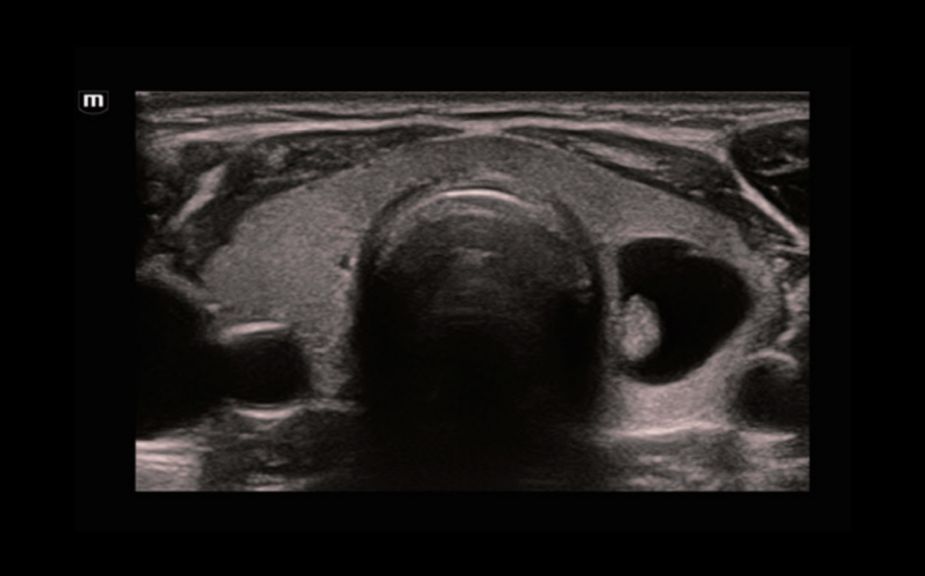

A Novel Approach of Vascular Hemodynamics: V Flow

The color coded vector arrows indicate the velocity magnitude and direction of blood cells. With an ultra-high frame rate, V Flow provides extremely vivid, accurate and angle-independent visualization of complex vascular hemodynamic profiles with comprehensive data information.

V Flow

A Novel Approach of Vascular Hemodynamics: V Flow

The color coded vector arrows indicate the velocity magnitude and direction of blood cells. With an ultra-high frame rate, V Flow provides extremely vivid, accurate and angle-independent visualization of complex vascular hemodynamic profiles with comprehensive data information.

V Flow